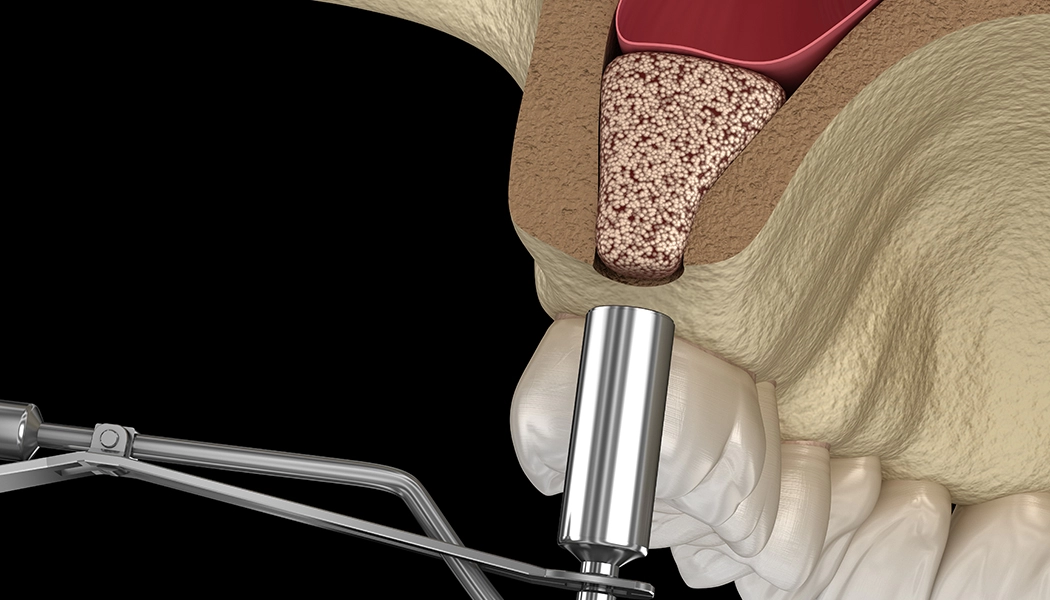

Показанием к проведению открытого синус-лифтинга является высота костной ткани менее 6 мм в области зубов, примыкающей к гайморовой пазухе. При открытом синус-лифтинге производится разрез слизистой, отслаивается слизисто-надкостничный лоскут, в передней стенке пазухи формируется перфорационное отверстие. Далее отслаивается слизистая самой пазухи, укладывается костный материал, после отверстие перекрывается специальной мембраной и слизисто-надкостничный лоскут ушивается.

Полное восстановление происходит через 4-6 месяцев и можно приступить к установке имплантатов или к постоянному протезированию. Процедуру синус-лифтинга возможно провести с одновременной установкой импланта. Благодаря этому сокращаются сроки лечения на несколько месяцев.